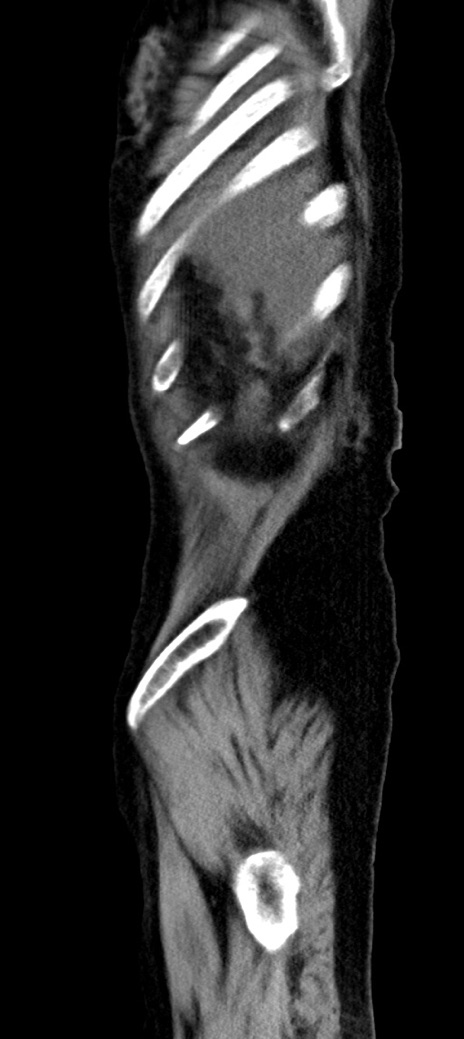

症例40(矢状断像)他院1日前

【症例】90歳代女性

【主訴】腹痛・嘔吐

【現病歴】 食欲低下、嘔吐があり昨日他院受診。肺炎と診断され入院となる。入院後より腹部全体に圧痛あり。胃管留置され経過みていたが、症状持続するため、

当院転院となる。

【既往歴】胸椎圧迫骨折、胆石症

【身体所見】腹部:中央に激痛あり、圧痛あり、反跳痛不明

【データ】WBC 17100、CRP 18.82